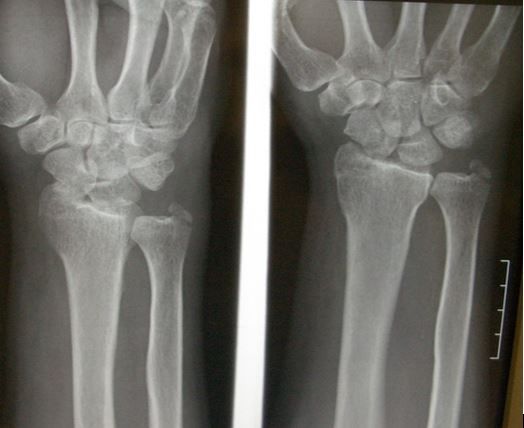

A 52-year-old man presents to the emergency department with a left wrist injury after a ground level fall. He states that he felt fine prior to slipping on a wet floor in his kitchen. There was no loss of consciousness, weakness, dizziness, chest pain, or preceding illness and he denies palpitations. He states that he did not hit his head and reports no neck or back pain or other injuries. He has no other complaints. There is no significant past medical history and there are no known risk factors for osteoporosis although he does smoke cigarettes.

On physical examination, the patient’s vital signs are normal and he appears to be in mild to moderate distress. Examination of the head, neck, back, and torso are all unremarkable. Examination of the extremities shows swelling and tenderness diffusely about the left wrist with intact pulses and sensation, intact skin, and no tense compartments. The elbow and hand are not tender.

His wrist x-ray is shown in Figure 1.